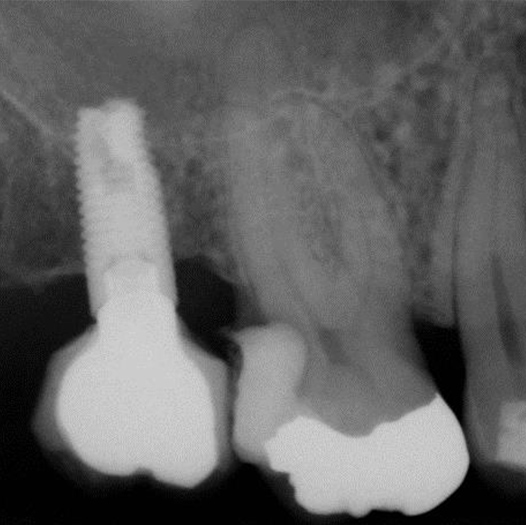

After

After Root Canal treatment